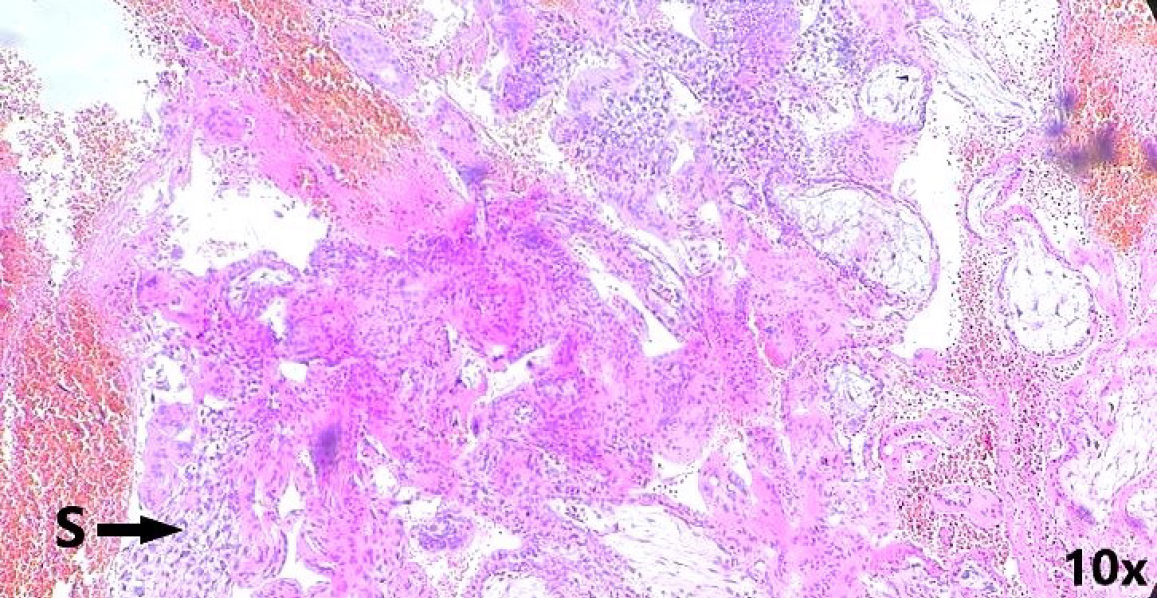

Figure 4 Histopathological examination.

Microscopic image of chorionic villi embedded within the hepatic tissue, confirming the diagnosis of intrahepatic ectopic pregnancy (hematoxylin and eosin staining, × 100).

Figure 5 Histopathological examination.

A: Magnification (× 40) magnification of hepatocytes (black arrow) and chorionic villi (orange arrow) with peripheral area of necrosis and hemorrhage; B: Cytotrophoblasts visualized (orange arrow) along with inflammatory infiltrates. S: Synctiotrophoblasts; H: Hepatocytes; CV: Chorionic villi; C: Cytotrophoblasts.